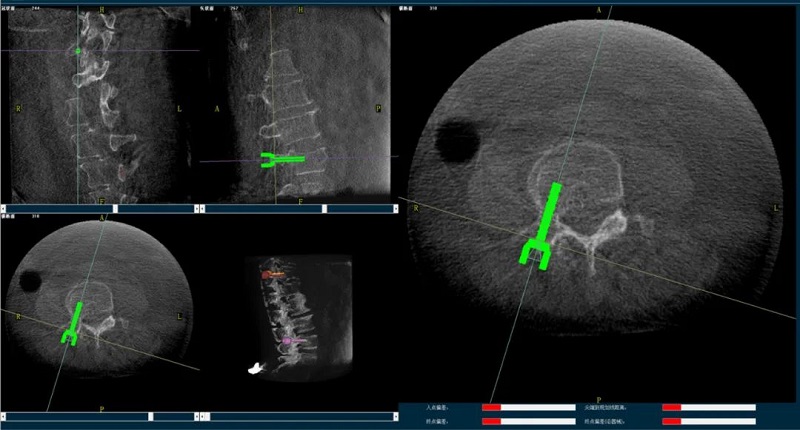

(2)醫(yī)生制定個性化的手術(shù)方案,在機器人導(dǎo)航界面上進行路徑規(guī)劃;

(3)根據(jù)設(shè)定好的的位置和入針方向,植入引導(dǎo)針;